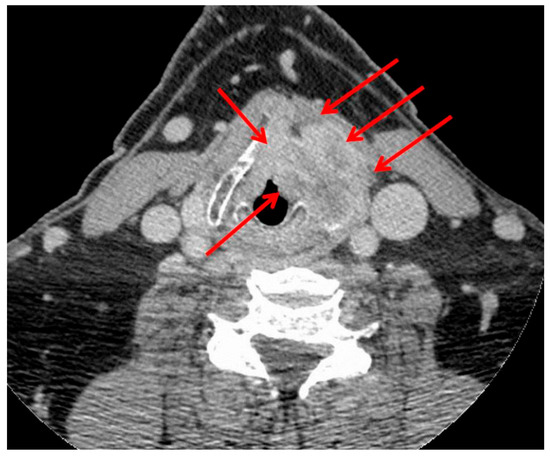

3.1. T4a Primary Tumors